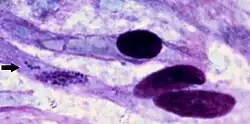

| Ehrlichia ruminantium bacteria within cell of brain of sheep that died of heartwater in Africa. | |

Heartwater (also known as cowdriosis, nintas, and ehrlichiosis) is a tick-borne rickettsial disease.[2] The name is derived from the fact that fluid can collect around the heart or in the lungs of infected animals.[3] It is caused by Ehrlichia ruminantium[4] (formerly Cowdria ruminantium)—an intracellular Gram-negative coccal bacterium (also referred to as Rickettsia ruminantium). The disease is spread by various Amblyomma ticks, and has a large economic impact on cattle production in affected areas. There are four documented manifestations of the disease. These are acute, peracute, subacute, and a mild form known as heartwater fever. There are reports of zoonotic infections of humans by E. ruminantium, similar to other Ehrlichia species, such as those that cause human ehrlichiosis.[5][6][7]

On post mortem examination, a light yellow transudate that coagulates on exposure to air is often found within the thorax, pericardium, and abdomen. Most fatal cases have the hydropericardium that gives the disease its common name. Pulmonary oedema and mucosal congestion are regularly seen along with frothy fluid in the airways and cut surfaces of the lungs. To definitively diagnose the disease, C. ruminantium must be demonstrated either in preparations of the hippocampus under Giemsa staining or by histopathology of brain or kidney.